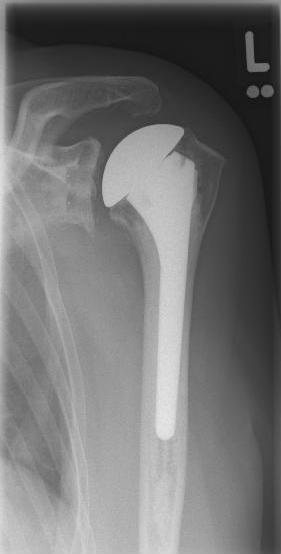

Abbildung2Abbildung1

left: X-ray image of an omarthrosis

right: X-ray of a healthy shoulder joint